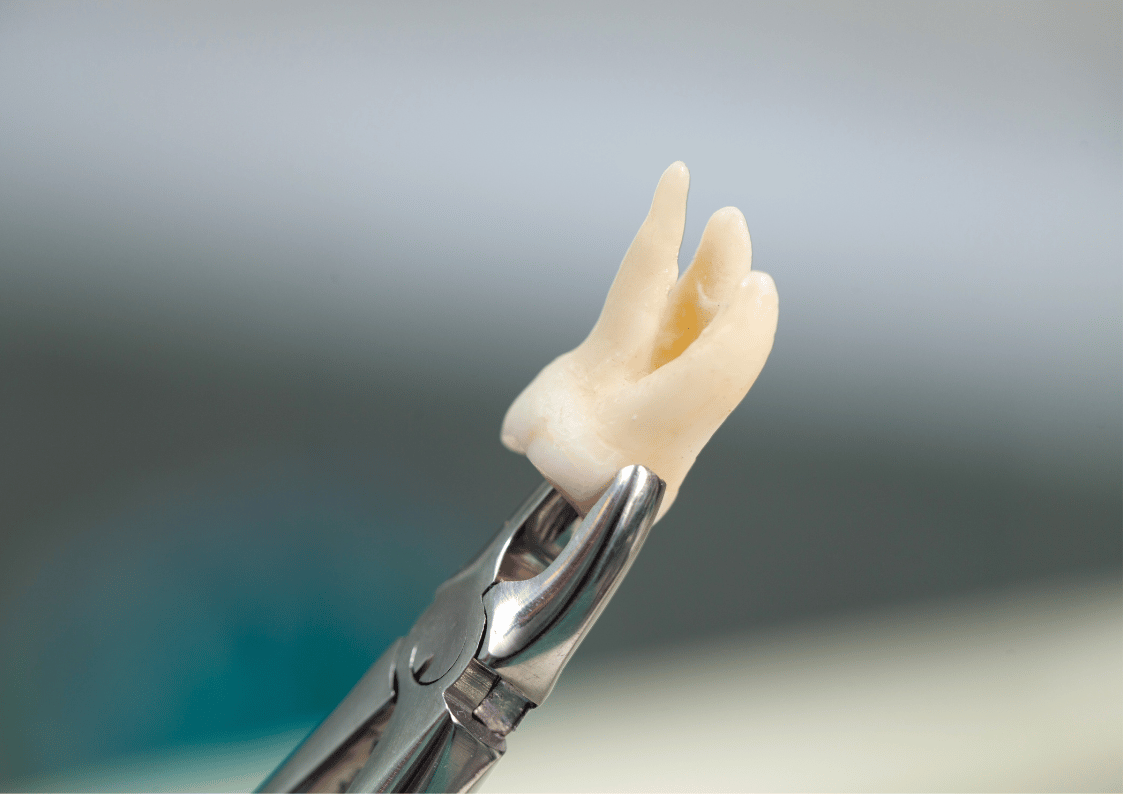

Wisdom Teeth Issues

- Surgical extractions (for impacted teeth).

- Simple extractions (for fully erupted teeth).